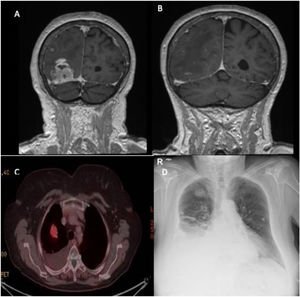

We present the case of a 79-year-old woman diagnosed with GBM after surgical resection of a right occipital lesion invading the transverse sinus, identified through cranial computed tomography (CT) and magnetic resonance imaging (MRI) (Fig. 1A, B), performed due to neurological symptoms. After partial resection, she underwent radiotherapy. Seven months later, radiological progression was observed, and a positron emission tomography-computed tomography (PET-CT) scan was performed for further evaluation.

(A and B) A magnetic resonance scan showed a right occipital lesion of rounded morphology close to the confluence of the venous sinuses, with invasion of the transverse sinus. (C) A positron emission tomography scan showed in the lung parenchyma a solid nodule in the right lung, which shows a slight increase in uptake, with a suspicious appearance. (D) A chest X-ray showed right pleural effusion and a pulmonary nodule in the right upper lobe.

The PET-CT scan (Fig. 1D) showed multiple solid nodules in the right lung parenchyma, suspicious for malignancy. The patient reported exertional dyspnea and right-sided rib pain without infectious signs. A chest X-ray revealed right-sided pleural effusion and a pulmonary nodule in the right upper lobe (Fig. 1C). Pleural fluid analysis confirmed an exudative effusion with lymphocytic predominance. Laboratory tests were within normal limits.